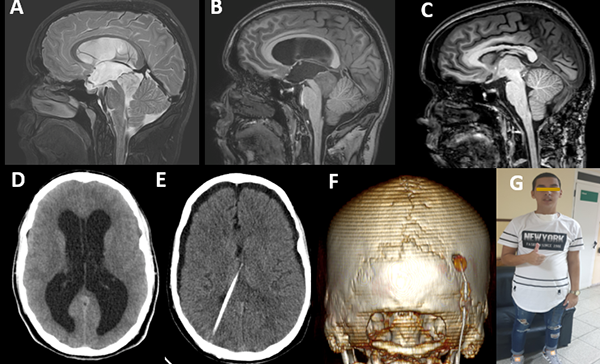

Se presenta un paciente masculino de 22 años de edad, de manualidad diestra y procedencia urbana, con antecedentes de cefalea holocraneal progresiva, nocturna y opresiva de 3 meses de evolución, asociada a vómitos ocasionales. Al examen físico se constató una puntuación según la Escala de Coma de Glasgow de 15 puntos y disartria como única manifestación positiva. La Tomografía Computarizada (TC), de urgencia, permitió observar dilatación de los ventrículos laterales y el tercer ventrículo, con edema periventricular y una lesión redondeada, isodensa y homogénea a nivel de la región pineal, correspondiente a una hidrocefalia obstructiva triventricular secundaria a un tumor en región pineal (figura 1 D). La RMI de cráneo de 3T evidenció además de la dilatación ventricular referida una lesión en región pineal hipointensa en la secuencia ponderada en T1 sin captación de contraste (figura 1 B) e hiperintensa en la secuencia ponderada en T2 (figura 1 A), de límites bien definidos con compresión y colapso del acueducto de Silvio, y efecto de masa sobre el vermis cerebeloso, que medía 26 mm x 27 mm x 23 mm en los diámetros anteroposterior, altura y transversal respectivamente. Se realizaron marcadores tumorales en suero y líquido cefalorraquídeo (LCR) los cuales resultaron negativos al igual que la citología del LCR.

Figura 1: A) Corte sagital de RMI preoperatoria potenciada en T2. Se observa la lesión hiperintensa en región pineal. B) Corte sagital de RMI preoperatoria potenciada en t1 con Gadolinio. Obsérvese la ausencia de captación de contraste y la presencia de la vena de Galeno por encima de la lesión. C) Corte sagital de RMI enT1 postoperatoria donde se aprecia la resección total de la lesión. D) TC axial postoperatoria observándose la hidrocefalia obstructiva a pesar de la tercer ventriculostomía endoscópica. E) TC axial donde se observa la colocación del catéter ventricular y la resolución de la hidrocefalia. F) Reconstrucción tridimensional de la TC postoperatoria donde se observa el área de la craneotomía. G) Fotografía postoperatoria del paciente.

Se practicó en un primer tiempo quirúrgico tercerventriculostomía endoscópica y biopsia de la lesión de región pineal la cual no fue concluyente. Durante el postoperatorio inmediato presentó, nuevamente, síntomas de hipertensión endocraneana, por lo que se realizó derivación ventrículo peritoneal (válvula de media presión) sin otras complicaciones (figura 1, D y E). El paciente mejoró los síntomas de hipertensión endocraneana, y 7 días después se le realizó el proceder quirúrgico definitivo a la lesión.

Bajo anestesia general orotraqueal y cateterización venosa central, línea arterial y sonda vesical se colocó al paciente en posición de semisentado (figura 2 A) y se fijó el cráneo con soporte de Mayfield. Luego de la asepsia y antisepsia con iodopovidona se realizó una incisión en línea media suboccipital desde la protuberancia occipital externa hasta la apófisis espinosa de C4 (figura 2 B). Se realizó disección de las partes blandas con electrobisturí sobre la línea media (ligamento nucal), y se desinsertó la musculatura paravertebral esqueletizándose la escama del occipital desde el inion hasta el borde posterior del agujero Magno. Las partes blandas se mantuvieron retraídas mediante 2 separadores de Adson. Se procedió a la realización de 2 trépanos a 3 cm lateralmente e inferiormente del inion, y con la combinación de fresado con drill de alta velocidad y el empleo de osteótomos de Kerrison, se completó una craniectomía de fosa posterior con el límite superior exponiendo el borde inferior de la prensa de Herófilo (figura 2 F). Se realizó hemostasia con empleo de cera hemostática. Se practicó una durotomía arciforme con base hacia la prensa de Herófilo y se colocaron puntos de tracción dural (figura 2 C). A partir de este momento, se empleó la visualización completamente endoscópica, en la cual el primer ayudante sostuvo el endoscopio de forma bimanual, mientras el cirujano principal realizó la disección microquirúrgica bimanual. Se procedió a la identificación, cauterización y sección microquirúrgica de las venas puentes de línea media (figura 2 D). Al progresar la disección infratentorial supracerebelosa de las densas bandas aracnoideas, se identificó la vena precentral, la cual fue cauterizada y seccionada de forma alejada de su entrada a la gran vena de Galeno (figura 2 E). Se identificó el tumor de límites bien definidos, consistencia sólida y de aspecto blanco-grisáceo. Se cauterizó la superficie tumoral y se procedió al debulking intratumoral mediante el empleo de la aspiración, la pinza bipolar y ponches de biopsia (figura 2 F). Se practicó hemostasia rigurosa empleando electrocoagulación bipolar y lavado continuo con solución salina tibia durante este paso. Al completar el debulking, se procedió a la disección microquirúrgica del tumor de las estructuras neurovasculares adyacentes incluyendo la gran vena de Galeno, las venas cerebrales internas, la porción superior del vermis cerebeloso, y finalmente la lámina cuadrigémina y pared posterior del III ventrículo. Al completar la resección tumoral se verificó una hemostasia rigurosa, y luego de abundante lavado con solución salina isotónica se aplicó material hemostático (Equicel) (figura 2 G). Se practicó un cierre dural con poliéster 4.0 mediante puntos separados y se cubrió la duramadre con poliuretano. Se cerraron las partes blandas en múltiples planos con poliéster 1.0 y la piel se suturó mediante puntos de mayo empleando nylon 2.0. El tiempo quirúrgico fue de 8 horas y el sangrado transoperatorio de 300 ml. El paciente permaneció intubado durante 24 horas en la Unidad de Cuidados Intensivos. Posteriormente, permaneció en dicha sala durante 5 días hasta que fue trasladado a sala abierta de Neurocirugía. Clínicamente presentó un síndrome de Parinaud (parálisis de la mirada vertical). Los estudios postoperatorios mostraron la resección total de la lesión (figura 1 C). La estadía hospitalaria fue de 30 días. El informe anatomopatológico fue concluyente de tumor del parénquima pineal de diferenciación intermedia. Evolucionó satisfactoriamente (figura 1 G).